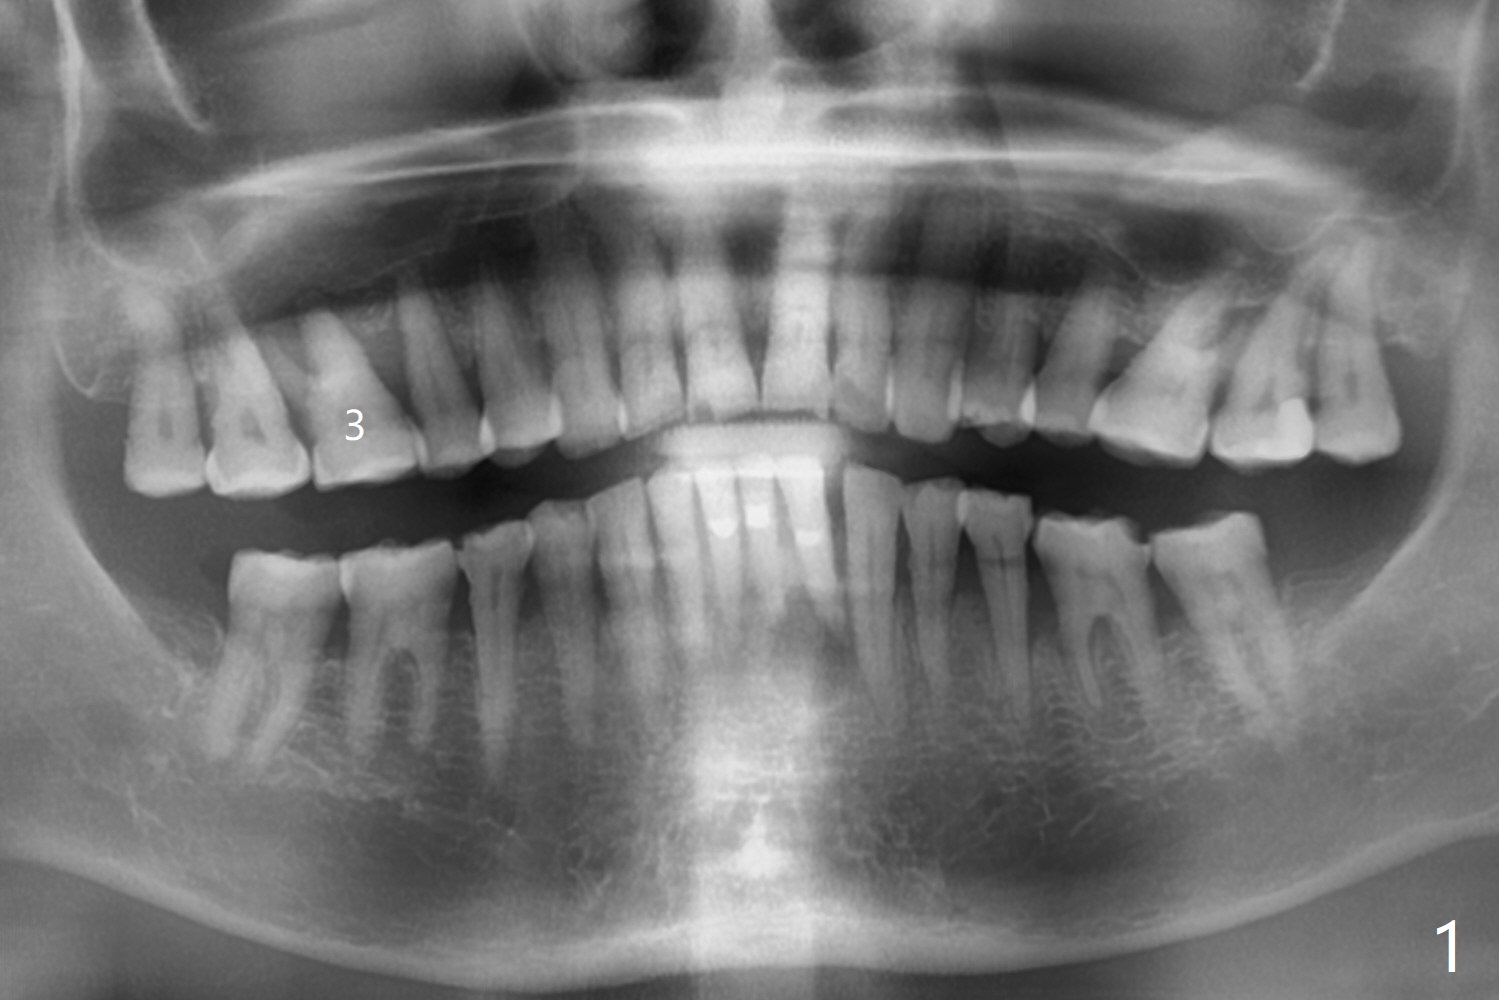

A 73-year-old woman with controlled diabetes has cold and hot sensitivity of the tooth #3. Although the bone loss is striking (Fig.1), mobility is I with the deepest pocket DL ~6 mm. Endo ice induces pain. Extraction and guided immediate implant appears to be the best option (Fig.2 (5x7mm FC)). Note the bone height (2.9 mm) and the thick sinus membrane (M, Fig.2') . B: buccal. Bony defect will be filled with sticky bone and held in place with Cytoplast, while PRF for sinus lift. Because she is afraid of implant, RCT, followed by SRP and possibly periodontal surgery, seems to be viable because of the straight, not-so-narrow canals (Fig.3-5). Due to time constraint, immediate implant will be done free hand. Use IS cassette, since there are 3 and 4 mm stoppers. Prepare FC dummy and water lifter for sinus lift.